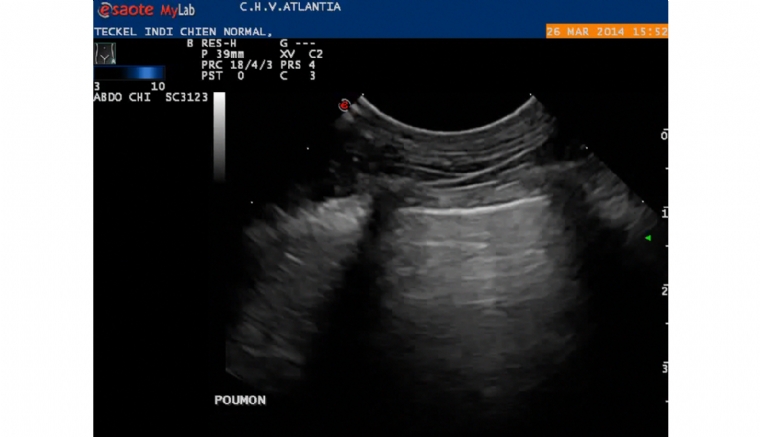

OEdème aigu pulmonaire cardiogénique du chien : décision d'hospitalisation, organisation et pronostic

Le vétérinaire doit connaître les critères de l'hospitalisation d'un chien présentant un oedème pulmonaire cardiogénique. La décision d'hospitaliser dépend de la gravité de l'oedème et peut découler de l'impossibilité de réaliser des traitements à domicil...